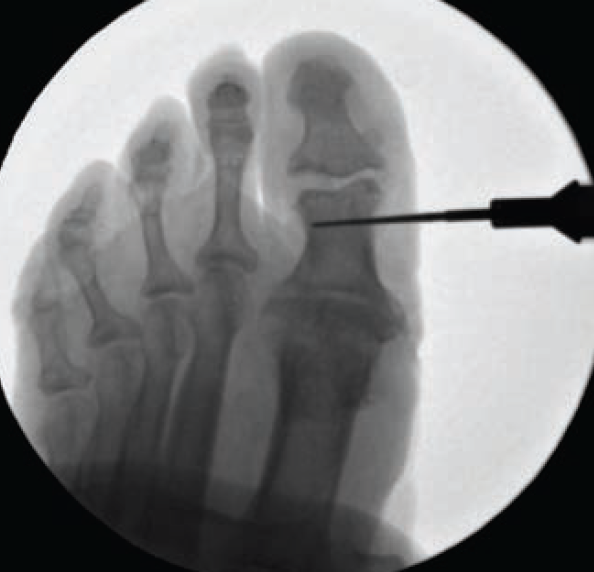

The patient is positioned supine, with the surgical extremity elevated for fluoroscopic imaging. The extremity is prepped to the ankle region, where a pneumatic tourniquet may be used based on surgeon preference and/or patient needs. A standard hallux block is performed. The instrumentation used in the procedure is shown in Figure 1.

The planned incision is drawn on the medial aspect of the hallux IPJ. The incision is approximately 2 cm to 3 cm long and is made at the junction of the plantar and dorsal skin (Figure 2). Using a no. 10 blade, a full-thickness incision is performed down to the level of the bone. Subperiosteal and capsular dissection is performed dorsally and plantarly on the proximal phalanx with a freer elevator. It is critically important to release all periosteal tissue from the IPJ in order to easily remove all resected bone. Dissection of the lateral subcapsular structures can be performed with a small McGlamry elevator (Figure 3). A powered, side-cutting Lindemann burr or Shannon burr is used to perform the arthroplasty (Figure 4). Mini C-arm fluoroscopy is used to confirm arthroplasty orientation (Figure 5). After orientation is confirmed, the surgeon inserts the burr from the medial cortex, through the medullary bone, and into the lateral cortex of the proximal phalanx. This technique is analogous to using a drill bit. Once through both cortices, the surgeon will “window-wash” to cut the dorsal and plantar cortices. A high-torque, low-speed power setting is preferred to enhance osseous resection and minimize soft tissue entrapment. After complete transection, the loose head of the proximal phalanx is easily removed through the incision (Figure 6), and the arthroplasty is confirmed by fluoroscopy (Figure 7). The wound is lavaged with copious normal sterile saline, and the void is then carefully backfilled with small vancomycin-impregnated calcium sulfate beads (Figure 8). The soft tissue envelope is then closed in a full-thickness fashion using 2-0 or 3-0 nonabsorbable monofilament suture. A combination of vertical mattress and simple interrupted suturing technique is used. The extremity is then cleansed and dried. Bacitracin ointment, nonadherent gauze, and a cohesive bandage are used to dress the surgical site.